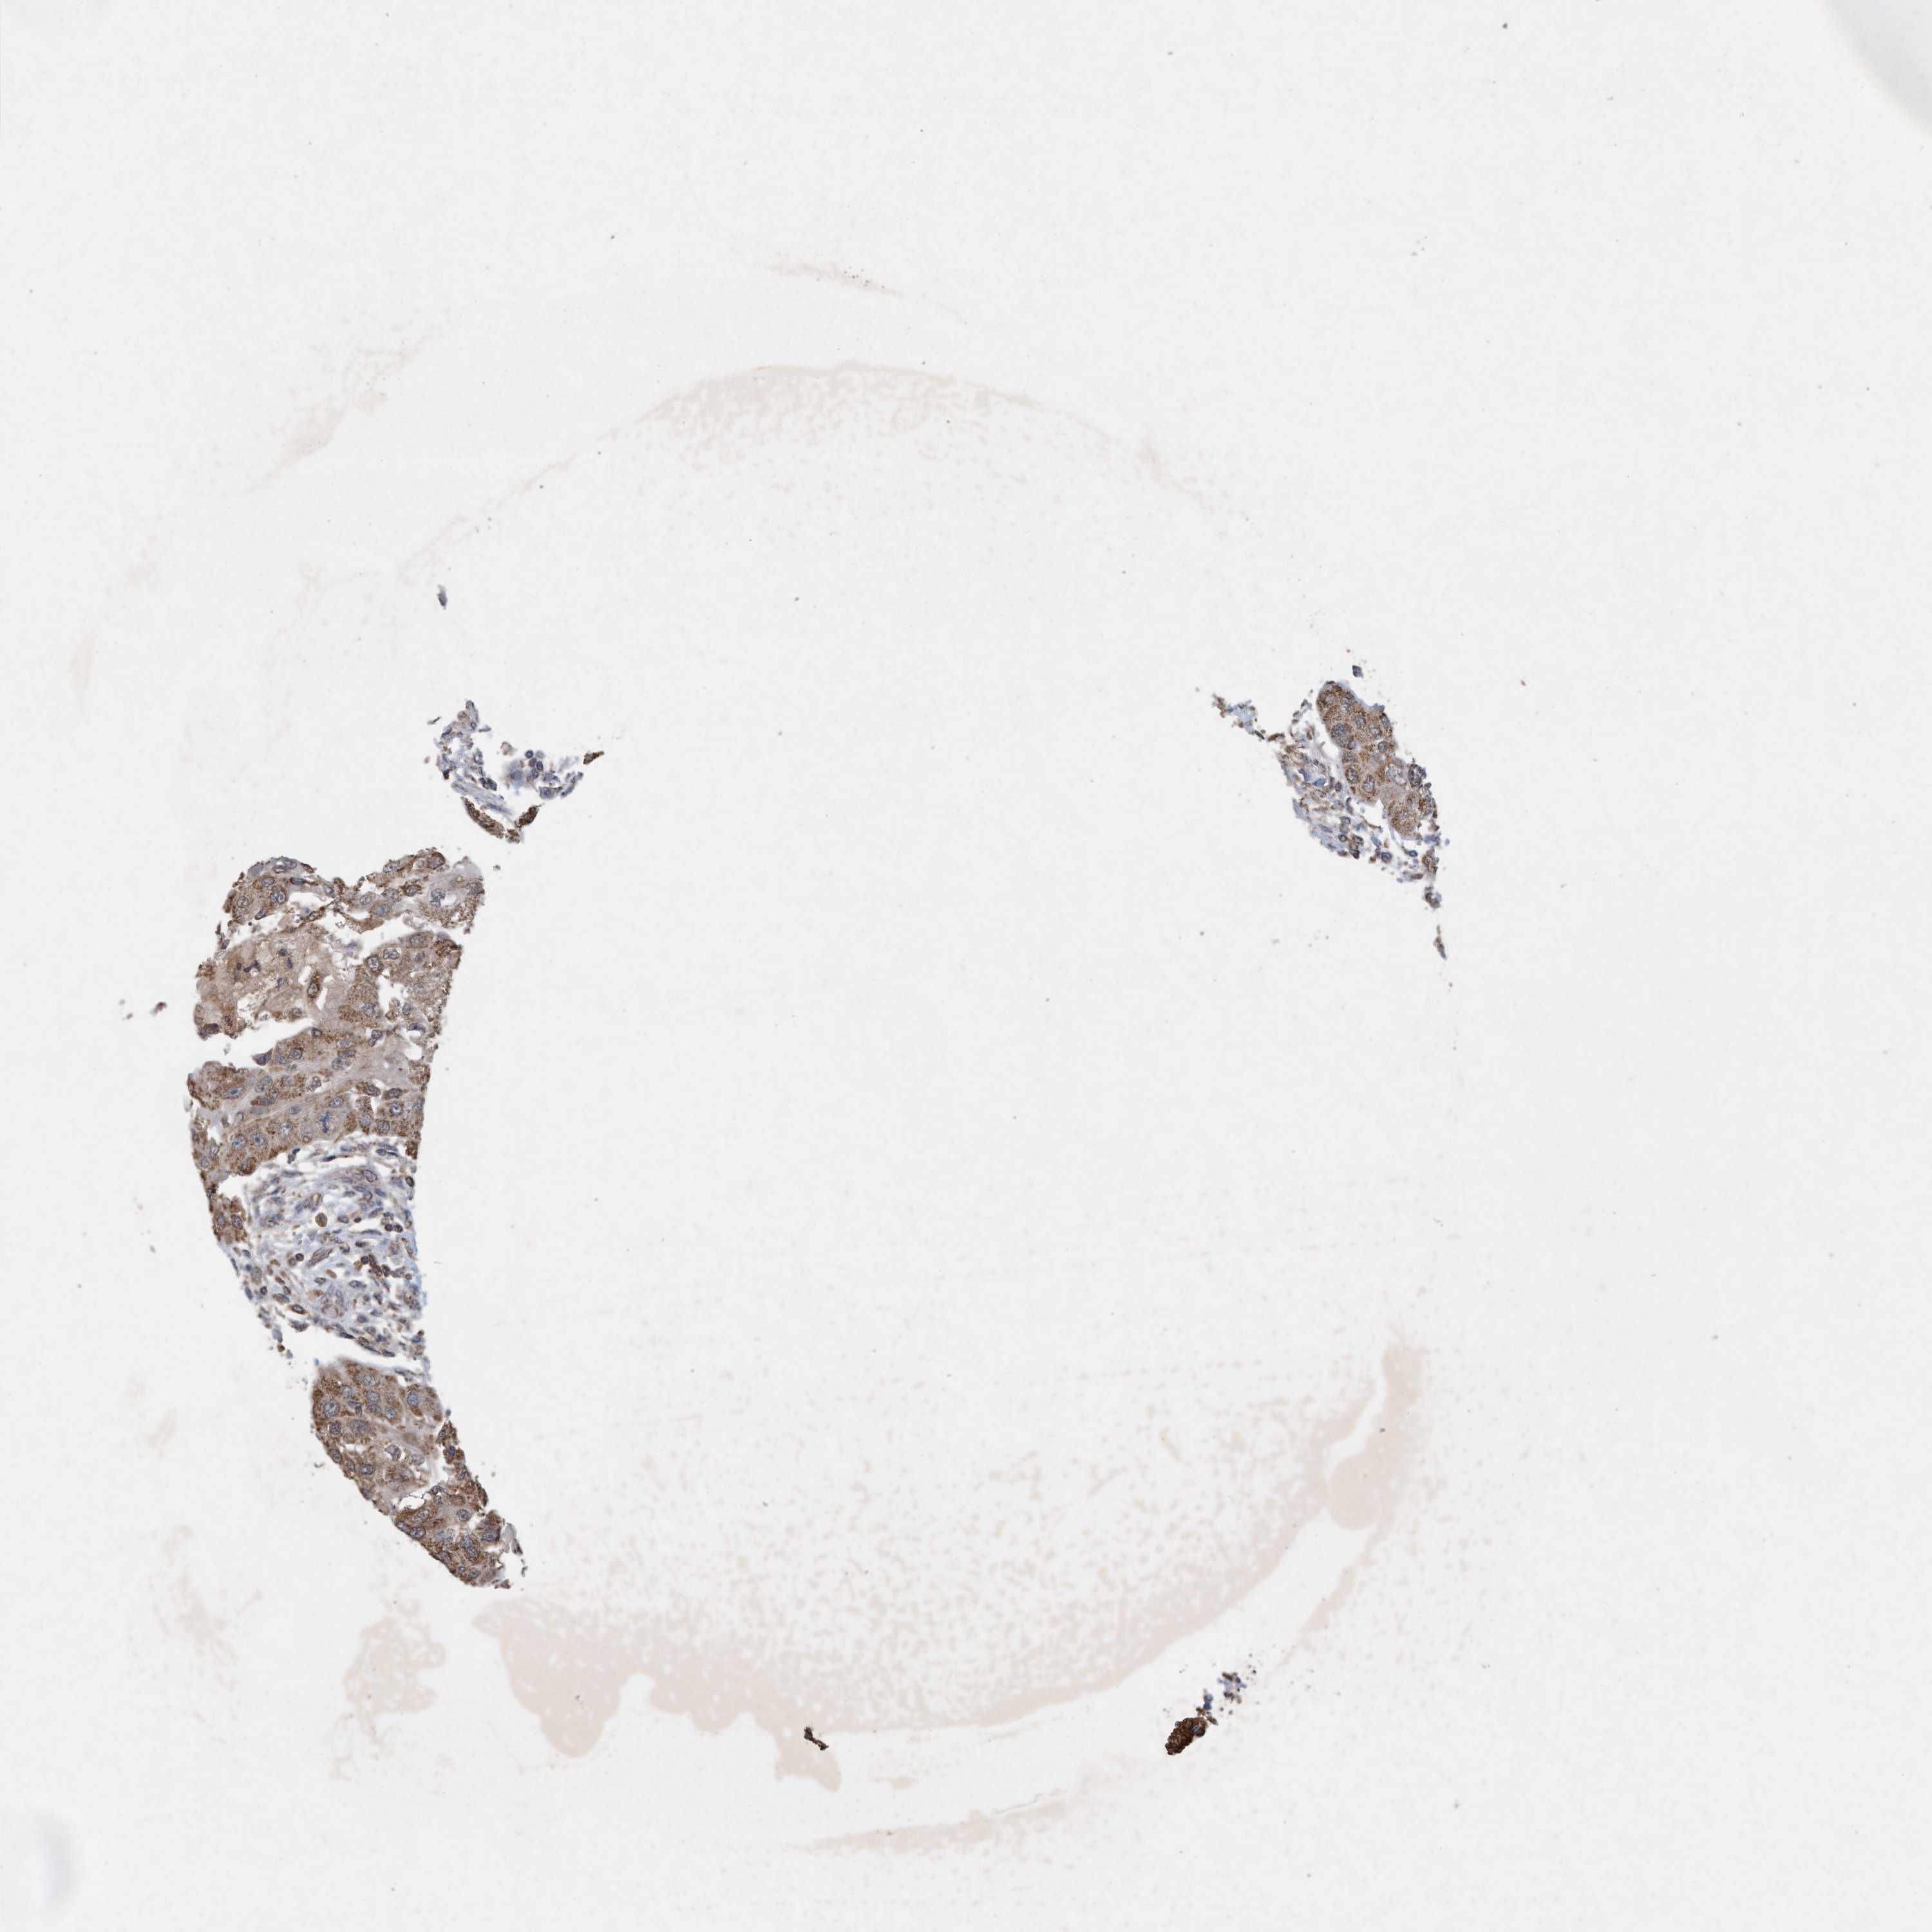

HEAD AND NECK CANCER - Protein expressioni

A mouse-over function shows sample information and annotation data. Click on an image to view it in a full screen mode. Samples can be filtered based on level of antibody staining by selecting one or several of the following categories: high, medium, low and not detected. The assay and annotation is described here.

Antibody stainingi

Antibody staining in the annotated cell types in the current human tissue is reported as not detected, low, medium, or high, based on conventional immunohistochemistry profiling in selected tissues. This score is based on the combination of the staining intensity and fraction of stained cells.

Each image is clickable and will lead to virtual microscopy that enables deeper exploration of all samples and also displays staining intensity scores, fraction scores and subcellular localization as well as patient and tissue information for each sample.

Antibody HPA023219

Staining

High

Medium

Low

Not detected

Intensity

Strong

Moderate

Weak

Negative

Quantity

>75%

75%-25%

<25%

None

Location

Nuclear

Cytoplasmic/membranous

Cytoplasmic/membranous,nuclear

Squamous cell carcinoma, NOS

Squamous cell carcinoma, metastatic, NOS

Adenocarcinoma, NOS